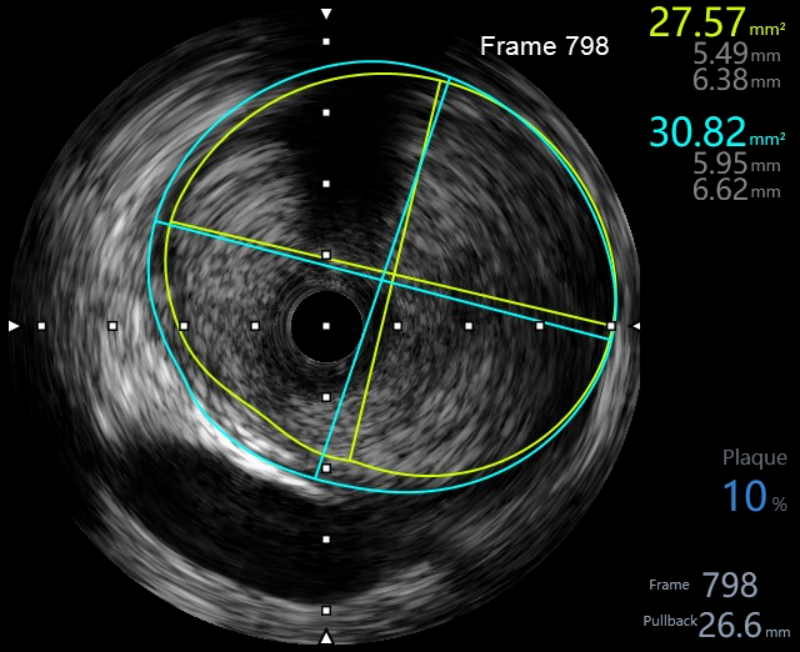

在惠州市中心人民醫(yī)院派駐博羅分院專家、博羅分院心血管內(nèi)科謝桂庭主任和謝志恒科副主任的帶領下,成功開展了博羅分院第一例冠狀動脈血管內(nèi)超聲(IVUS)檢查。術中行冠狀動脈血管內(nèi)超聲(IVUS)檢查:回旋支中段瘤樣擴張,少量血栓影,最大管腔直徑約6mm,未見夾層、血腫(圖4、5)。患者病變?yōu)楣诿}瘤樣擴張并血栓形成,予抗栓等治療后患者好轉(zhuǎn)出院。

文章配圖

(圖4)